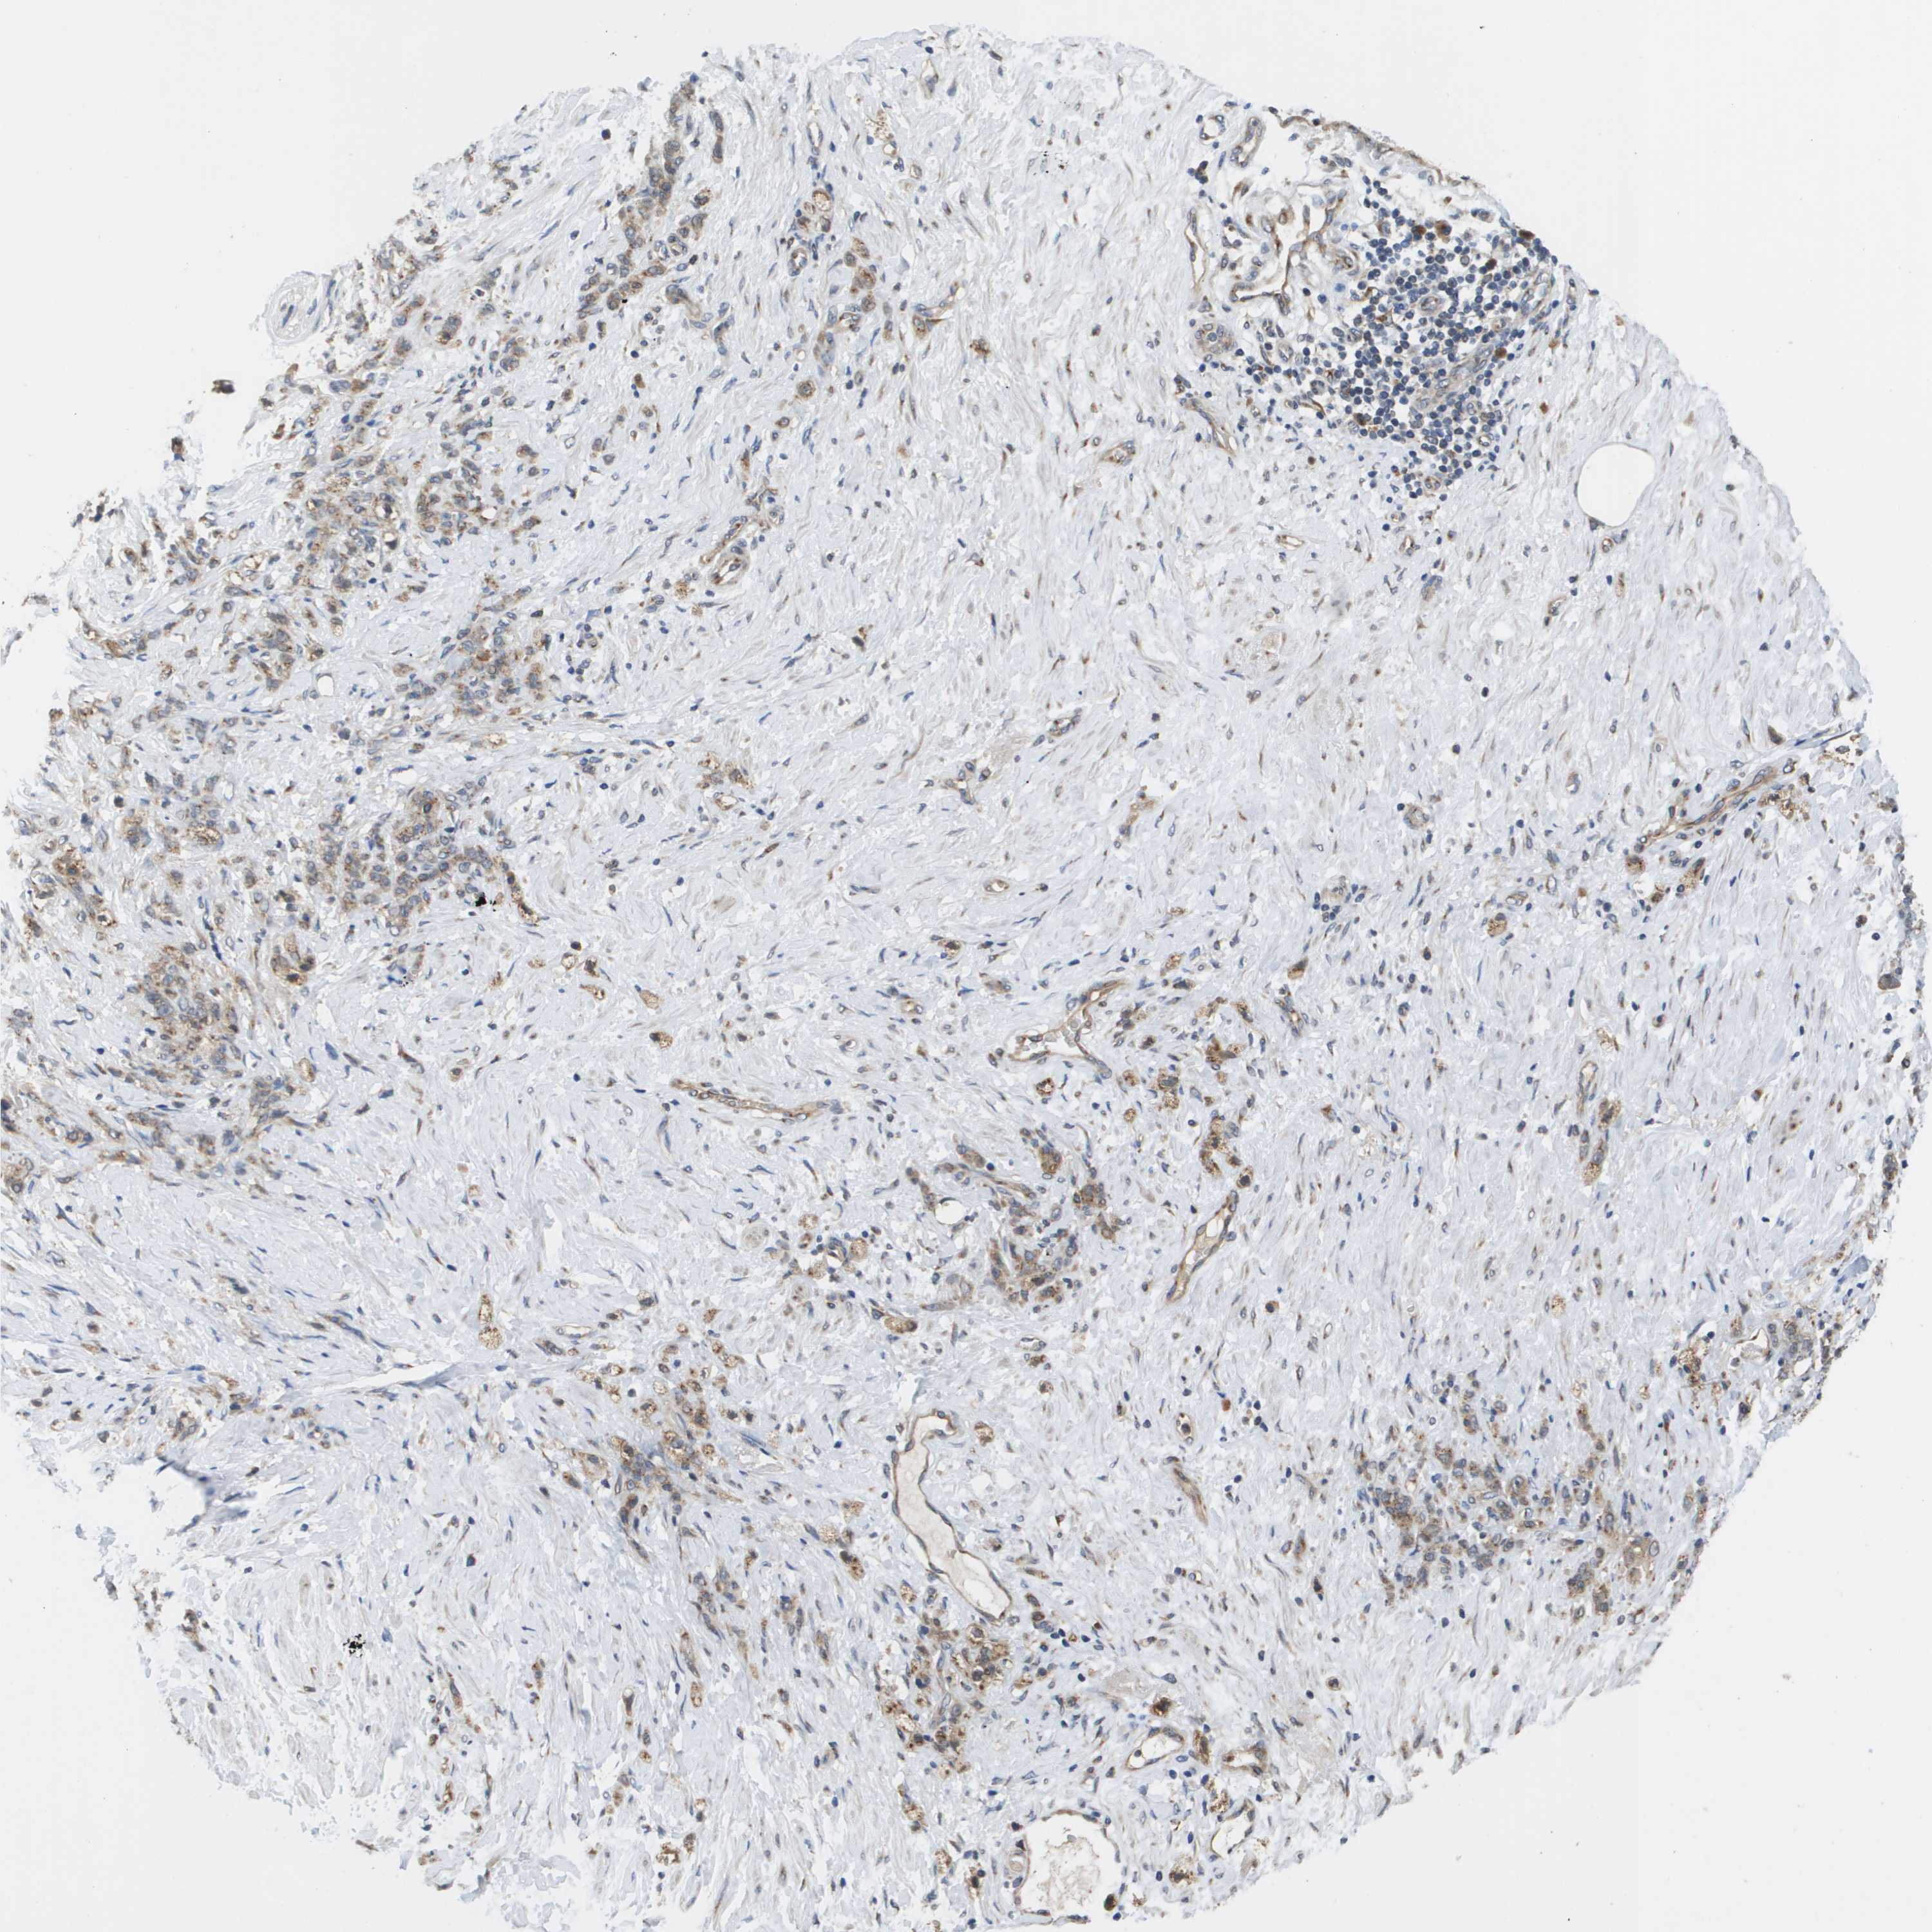

STOMACH CANCER - Protein expressioni

A mouse-over function shows sample information and annotation data. Click on an image to view it in a full screen mode. Samples can be filtered based on level of antibody staining by selecting one or several of the following categories: high, medium, low and not detected. The assay and annotation is described here.

Note that samples used for immunohistochemistry by the Human Protein Atlas do not correspond to samples in the TCGA dataset.

Antibody stainingi

Antibody staining in the annotated cell types in the current human tissue is reported as not detected, low, medium, or high, based on conventional immunohistochemistry profiling in selected tissues. This score is based on the combination of the staining intensity and fraction of stained cells.

Each image is clickable and will lead to virtual microscopy that enables deeper exploration of all samples and also displays staining intensity scores, fraction scores and subcellular localization as well as patient and tissue information for each sample.

Antibody HPA006277

Antibody HPA006507

Antibody CAB017027

Staining

High

Medium

Low

Not detected

Intensity

Strong

Moderate

Weak

Negative

Quantity

>75%

75%-25%

<25%

None

Location

Nuclear

Cytoplasmic/membranous

Cytoplasmic/membranous,nuclear

Adenocarcinoma, NOS

Adenocarcinoma, High grade